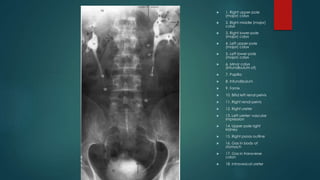

 1. Right upper-pole

(major) calyx

 2. Right middle (major)

calyx

 3. Right lower-pole

 4. Left upper-pole

 5. Left lower-pole

 6. Minor calyx

(infundibulum of)

 7. Papilla

 8. Infundibulum

 9. Fornix

 10. Bifid left renal pelvis

 11. Right renal pelvis

 12. Right ureter

 13. Left ureter: vascular

impression

 14. Upper pole right

kidney

 15. Right psoas outline

 16. Gas in body of

stomach

 17. Gas in transverse

colon

 18. Intravesical ureter